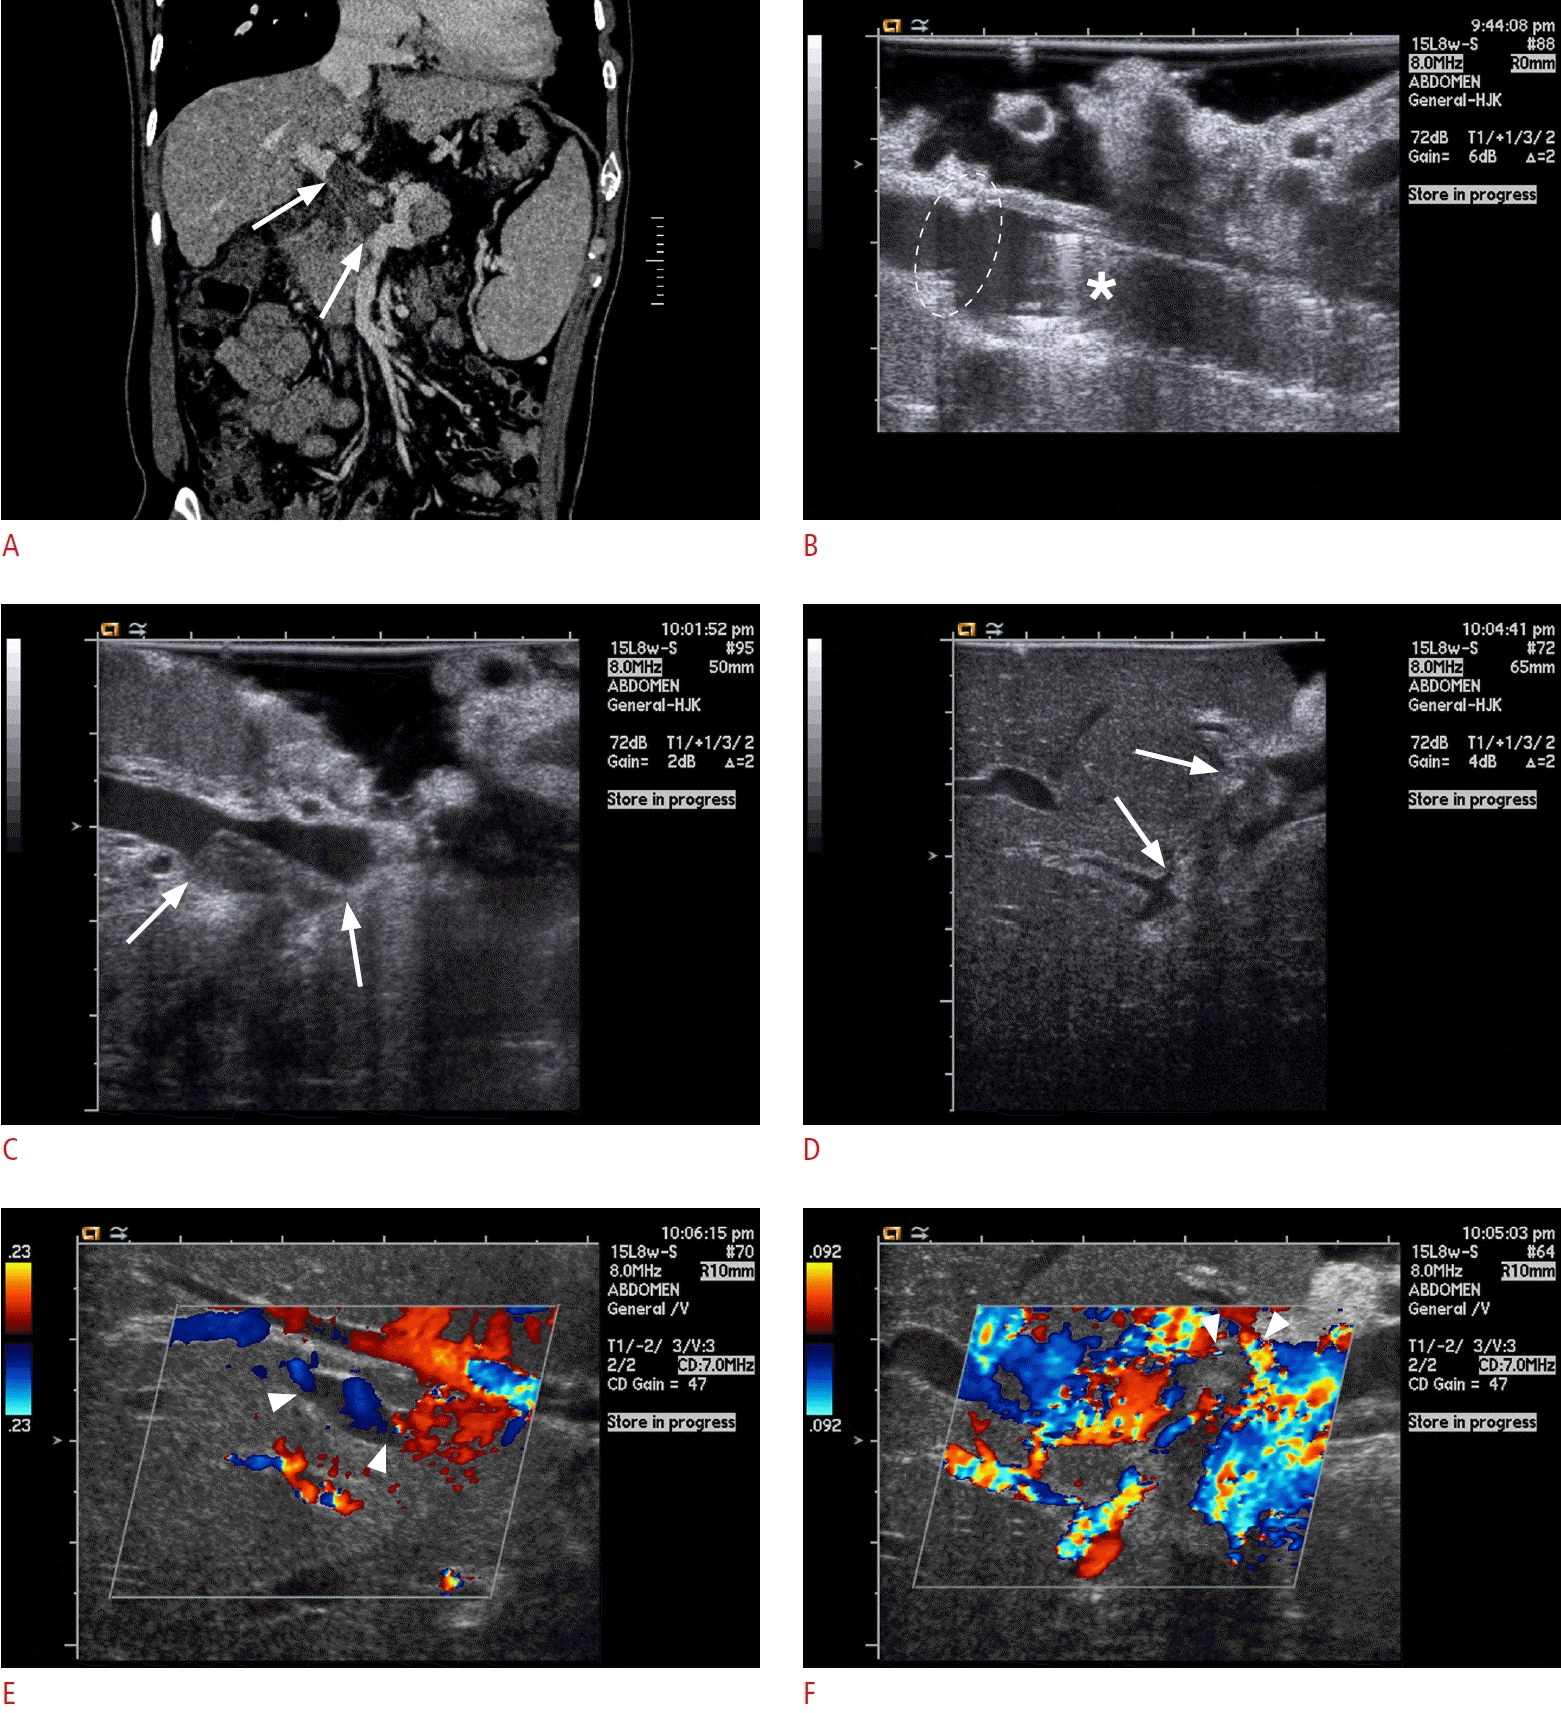

Fig. 5.

Size discrepancy between the donor and recipient portal veins, without significant stenosis.

A. Grayscale intraoperative ultrasonograms show abrupt caliber change at the anastomosis (arrows). B, C. Color Doppler ultrasonograms show aliasing effect at the donor’s portal vein due to jet flow induced by the size discrepancy. Doppler spectrogram measures peak velocity of the portal flow at both sides of the donor’s (B) and recipient’s (C) portal veins. It reveals acceleration of peak portal flow velocity, approximately two times, through the portal vein anastomosis. GPV, graft portal vein; RPV, recipient portal vein.

Fig. 6.

Portal vein thromboembolus.

A. Coronal computed tomography image during the portal venous phase, obtained for preoperative work-up, shows thrombus (arrows) from the portal confluence to extrahepatic portal vein. B. Grayscale intraoperative ultrasonogram shows no residual thrombus at the extrahepatic portal vein after surgical thrombectomy and portal vein stent (asterisk) placement. Portal vein anastomosis is also noted (dashed circle). C, D. However, intraoperative ultrasonograms reveal partial thrombus at the intrahepatic portal branch, seen as filling defect with mild echogenicity (arrows). E, F. Color Doppler intraoperative ultrasonograms show partial void of color flow signal at the portal branches with thrombus (arrowheads). It would be supposed that the thrombus at the extrahepatic portal vein may have been incompletely removed and migrated distally after the anastomotic reconstruction and reperfusion.